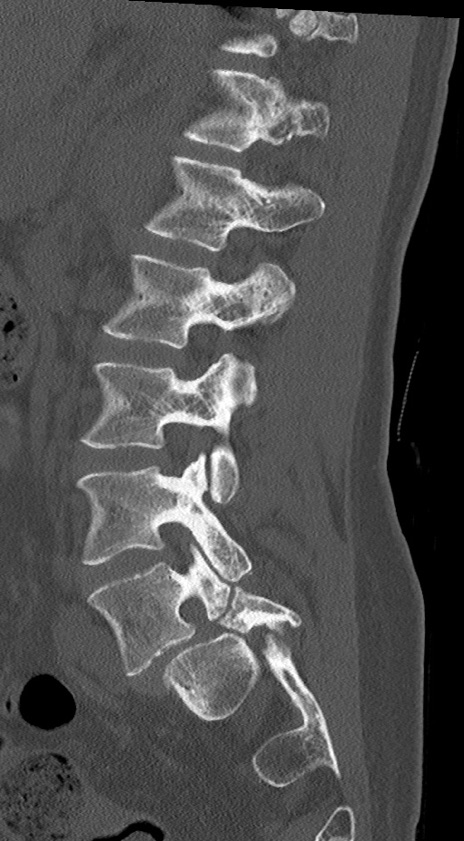

【整形】TIPS症例4 腰椎CT(矢状断像)

腰椎CT

冠状断像